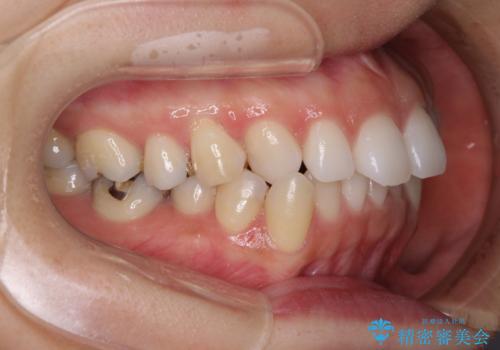

- 口元の突出感と口の閉じにくさを気にして来院された患者様です。

上下左右第一小臼歯4本を抜歯し、ワイヤー装置にて口元を引っ込めるよう矯正治療を行うこととしました。

奥歯が前方に傾斜していることで深く咬みこむ(ディープバイト)状態であったので、なかなか抜歯したスペースが閉じず、様々な方法でディープバイトを改善しながら治療を進めていくこととなりました。